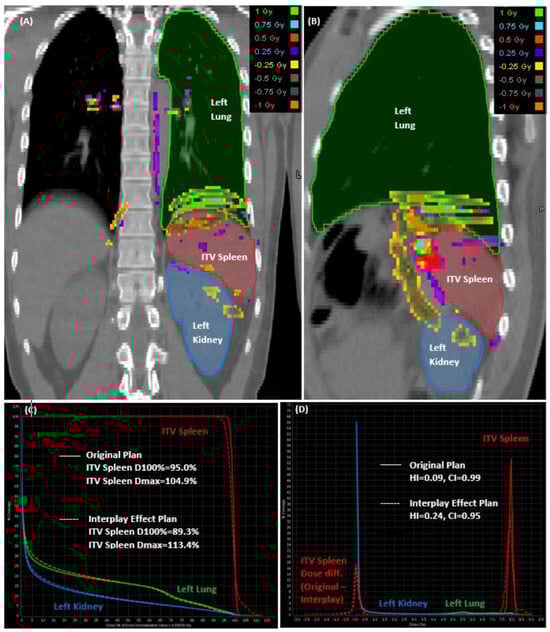

A virtual phantom was created using a patient’s CT images to mimic splenic motions at various displacements of ±3 mm, ±6 mm, ±8 mm, and ±10 mm in the inferior to superior direction. To achieve this, a specialized image manipulation software called ImSimQA (version 4.3.2.) (Oncology Systems Limited, Shropshire, UK) was employed. The software created deformation vector fields, which were then applied to produce artificial CT images with precisely known deformations of ±0.1 mm uncertainty. Figure 1 illustrates a patient case with simulated splenic motion with an associated magnitude of 10 mm ± 0.1 mm in the superior direction, depicted by overlaid deformation vector fields on CT images before Figure 1A and after Figure 1B manipulation. To achieve this deformation, a set of 10 anchor points was strategically placed to deform the upper abdomen region, including the diaphragm, spleen, and liver, by known amounts.

Figure 1. A deformed image of before (A) and after (B) is shown with 10 anchor points. Cross hair reads a net deformation of 9.94 mm for the spleen in superior direction.